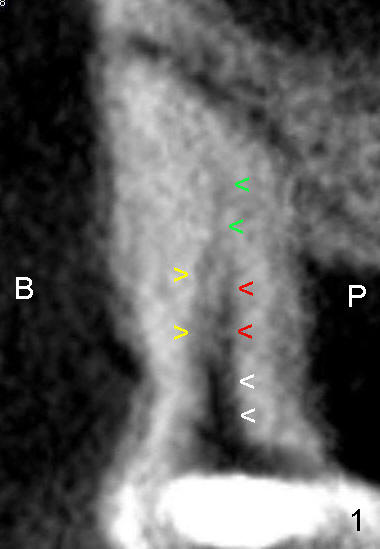

几周后,他回来完成根管治疗,带来CT光盘。匆匆忙忙打开看,结论是没有MB2:MB开始是一个根管(图一(B:颊侧,

P:鄂侧)白箭头),然后分成两个(红箭头与黄箭头),很快又融合成一个根管(绿箭头)。